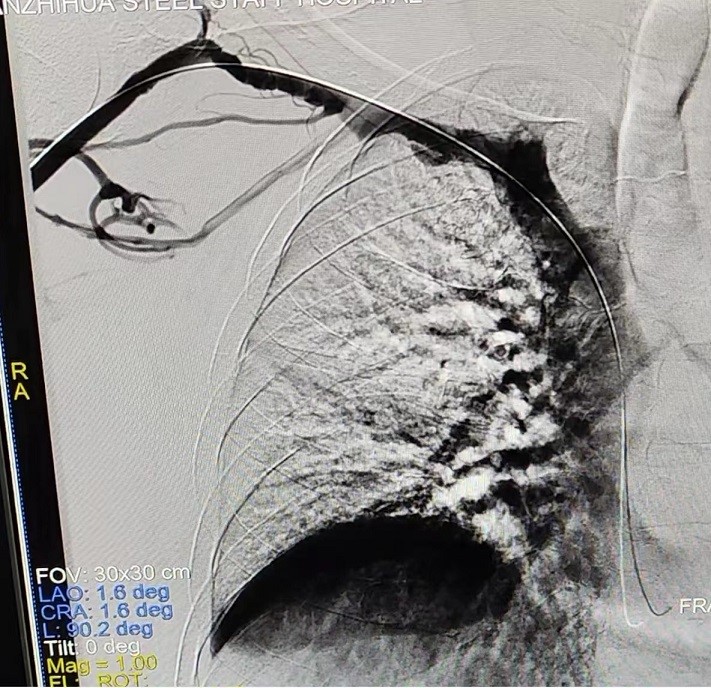

手術(shù)中,主刀醫(yī)生唐靜通過DSA順利對人工血管中形成的血栓進(jìn)行了取栓。之后,在中心靜脈造影下,發(fā)現(xiàn)患者中心靜脈外周有2cm的狹窄,尤其是右鎖骨下靜脈得狹窄已經(jīng)嚴(yán)重到幾乎閉塞,針眼大小的縫隙僅能容下導(dǎo)絲通過。經(jīng)過反復(fù)嘗試與不懈努力,終于將導(dǎo)絲置入,并用12 *40mm的球囊擴(kuò)張,右鎖骨下靜脈成功開通,患者透析的通道打開了。術(shù)后,家屬看著消腫的手臂感激萬分,眼淚奪眶而出。

術(shù)后造影顯示:右鎖骨下靜脈狹窄完全打開